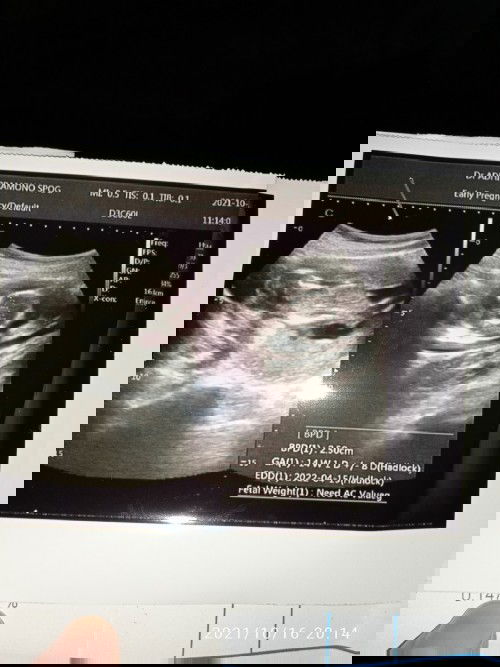

jumat kmrin saya usg dgn usia janin 13w4d. alhamdulillah dokternya menjelaskan dengan detail bagaimana keadaan janin, mulai dari detak jantung, air ketuban, sampai saya gemes ngeliat kaki dd yg aktif bergerak2 hehee.. saran saya sebaiknya ganti dokter yg lebih komunikatif bun, agar mendapat penjelasan yg lebih detail tentang tumbuh kembang si buah hati 😍🤗 semangat bun kita hplnya berdekatan

2D bun

Maksudnya gk kedengeran waktu USG ya bun ? klw emang iya terus dokternya ngomong gimana ? normalnya ddj itu klw lewat USG 7w aja udah kedengeran loh bun wlwpun belum trlalu jelas, hasil USG bunda itu malah udah 14w1d klw belum kedengeran juga djj itu gk wajar bun, cba ganti dokter bun